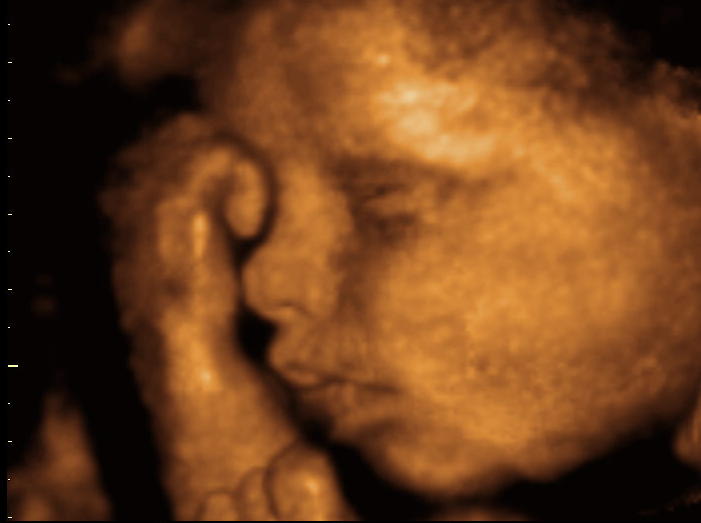

3d Scanner Image 3d Sonogram